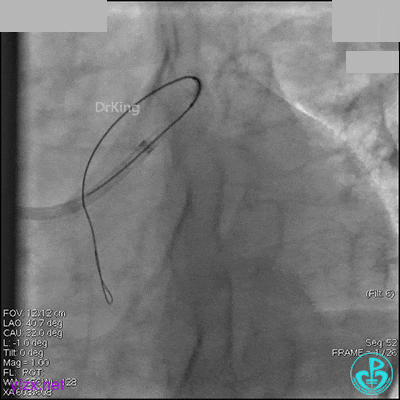

AL 1.0指引导管到位,简单短时尝试导丝不能顺利通过前降支或回旋支病变。改变策略处理右冠脉病变,计划植入2枚支架。AL指引导管到位,Sion blue导丝到达右冠脉远端。导丝通过后1.5mm及2.5mm球囊14~16atm充分扩张中段病变。

右冠脉中段充分扩张后欲植入3.5×38mm支架时,支架难以通过中远段扭曲处,且指引导管、导丝弹出飞扬。反复尝试导丝重新到达右冠脉远端时通过不顺利,局部造影剂滞留,远端血流接近3级。